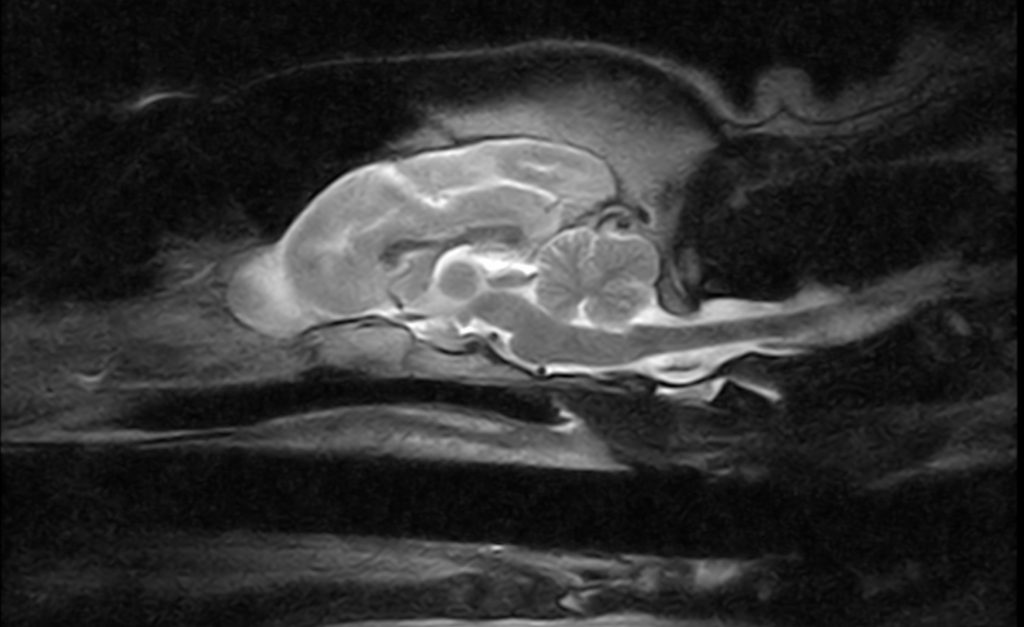

Affordable Solutions Veterinary Diagnostic Solutions to meet the needs of your practice while increasing your profitability. Contact a representative today and learn how we can help you advance your diagnostic capabilities while improving your financial sustainability. Veterinary CT Solutions Veterinary MRI Solutions